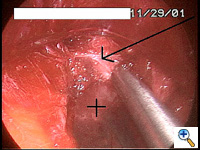

Once the tunnel reaches the sternum, the endoscopic tunneling device is utilized to visualize the clamp entering the interspace of maximal pectus depth and passing retrosternal (Figure 7). At the level of the sternum, these tunnels go retrosternal and communicate with each other. Ideally, even after entering the interspace, the tunnel stays extrapleural. The endoscopic view of the tunnel allows visualization of the safe passage of the clamp under the sternum and anterior to the pericardium. The mediastinum and pericardium can be seen pulsating posterior to the clamp. Two monitoring screens are utilized in order to allow excellent visualization by both the surgeon and assistant (Figure 8). Eventually, the larger curved clamp is easily passed under the sternum (Figure 9). This clamp is thus passed through one midaxillary skin incision and out the other midaxillary skin incision.

The clamp is then opened and used to grasp an umbilical tape and pull the tape through the tunnel (Figure 10). This umbilical tape is tied to two more umbilical tapes so that one tape can be used to pull a flat mediastinal tube through the tunnel and the second umbilical tape can act as a back-up. One umbilical tape is tied to a flat mediastinal tube. Then, this flat mediastinal tube is lubricated (Figure 11) and pulled through the tunnel and used to gently dilate the tunnel. The tunnel pathway is then endoscopically inspected to confirm hemostasis and satisfactory position of the flat mediastinal tube (Figure 12 ).